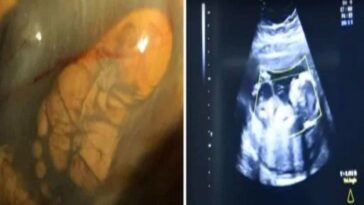

in Ιστορίες Πήγε στο Νοσοκομείο Ουρλιάζοντας από τον Πόνο. Όταν της έκοψαν το Παντελόνι, δεν είχε ιδέα ότι ήταν έγκυος μέχρι την στιγμή που γέννησε!